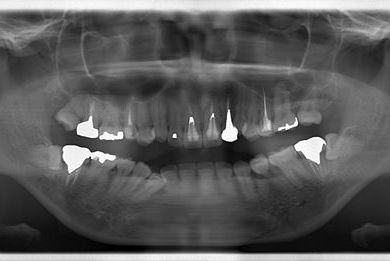

| 性別/年齢 | 女性 / 31歳 | ||||||||||||||||||||||||||||||||

| 治療方針 | セラミック治療により、審美的回復を行う。 | ||||||||||||||||||||||||||||||||

| 治療内容 | CAD/CAMオールセラミッククラウン1本(オールセラミック用土台1本)、オールセラミッククラウン2本(オールセラミック用土台2本) | ||||||||||||||||||||||||||||||||

| 総治療費 | 341,775円 | ||||||||||||||||||||||||||||||||

| 治療期間 | 10ヶ月 |